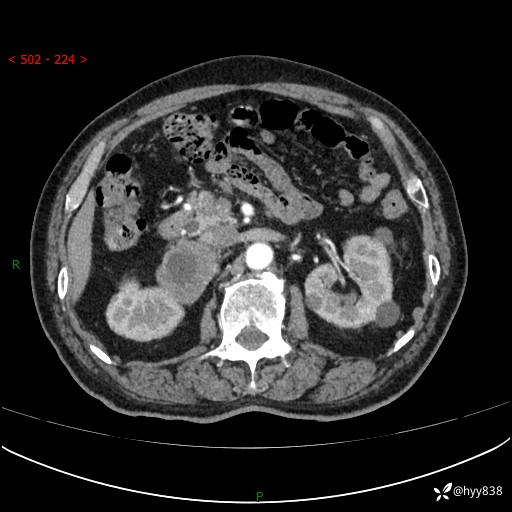

【患者信息】:76岁/男

【主诉】:检查发现右侧肾上腺占位6天

【现病史及既往史】:患者6天前体检发现右侧肾上腺占位,无腰痛,无放射痛,无尿频、尿急、尿痛及肉眼血尿,无畏寒、发热,无恶心、呕吐,今为求进一步治疗,遂来我院就诊,门诊拟“右侧肾上腺占位”收住入院。 起病以来,患者精神、饮食、睡眠可,大小便如常,体力体重无明显变化。

【检查】:肾上腺CT平扫+增强